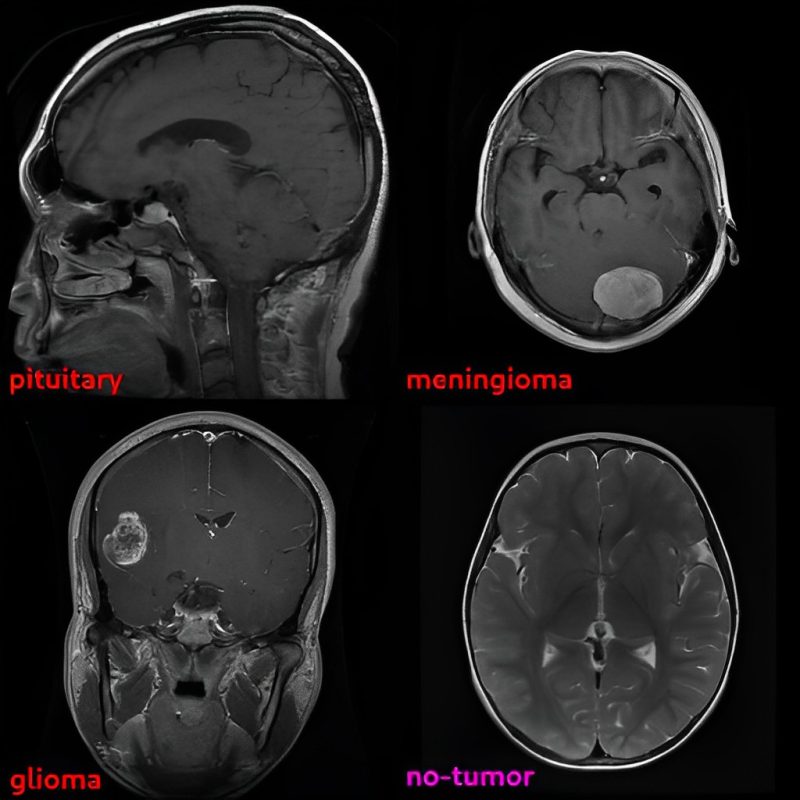

artificial intelligence